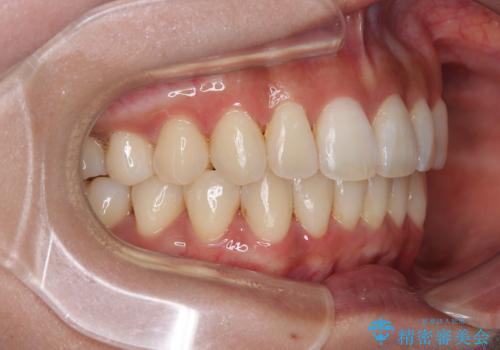

【モニター】上顎前突と奥歯の鋏状咬合 補助装置を用いたインビザライン矯正治療

奥歯の咬み合わせを事前に望ましい位置に改善したことで、インビザライン単独では改善が最も困難な状況を排除することができ、非常に理想的な仕上がりとなりました。